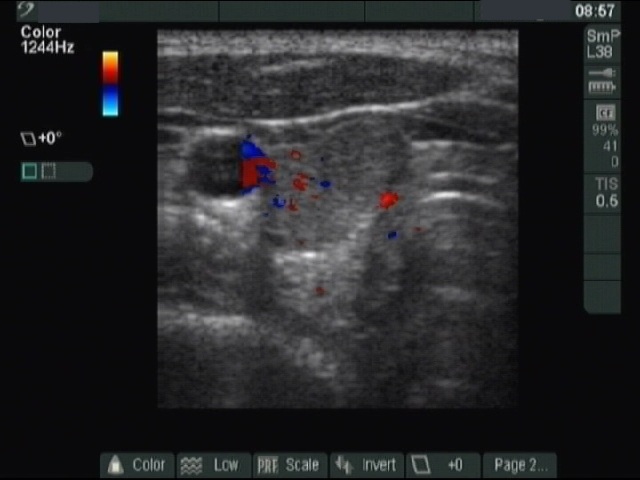

Benign nodular hyperplasia - Case 43. |

Clinical presentation: a 26-year-old woman was presented with a newly discovered nodule.

Palpation: a nodule in the right side of the isthmus.

Ultrasonography: a moderately hypoechogenic nodule in the isthmus. The nodule exhibited microcalcifications. The vascularization was not specific. Neither a halo sign nor perinodular blood flow was observed.